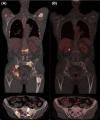

Multiple large osteolytic lesions in a patient with systemic mastocytosis: a challenging diagnosis

Patients with advanced variants of Systemic Mastocytosis may develop destructive bone lesions when massive mast cell (MC) infiltrates are present. Finding of large osteolyses in indolent systemic mastocytosis, typically characterized by low MC burden, should prompt investigations for an alternative explanation.